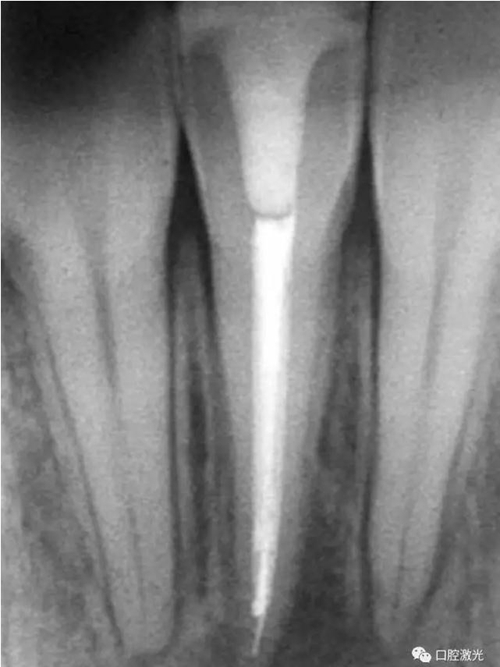

46治療前X光片